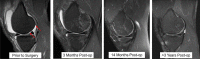

Purpose: To describe a technique for fixation of large isolated chondral fractures of the knee and present 3 cases where large chondral fragments without osseous attachment were fixed successfully with chondral darts and biologic adhesive.

Results: Successful results and complete healing was obtained in all 3 patients. This procedure can be done in the setting of concurrent injury, such as anterior cruciate ligament tear, using single- or multistaged chondral repair and ligament reconstruction techniques.

Conclusion: Isolated chondral fragment repair techniques provide the orthopaedic surgeon an additional option for treating these challenging injuries. Primary fixation can be accomplished for what have been historically considered "unsalvageable" fragments.